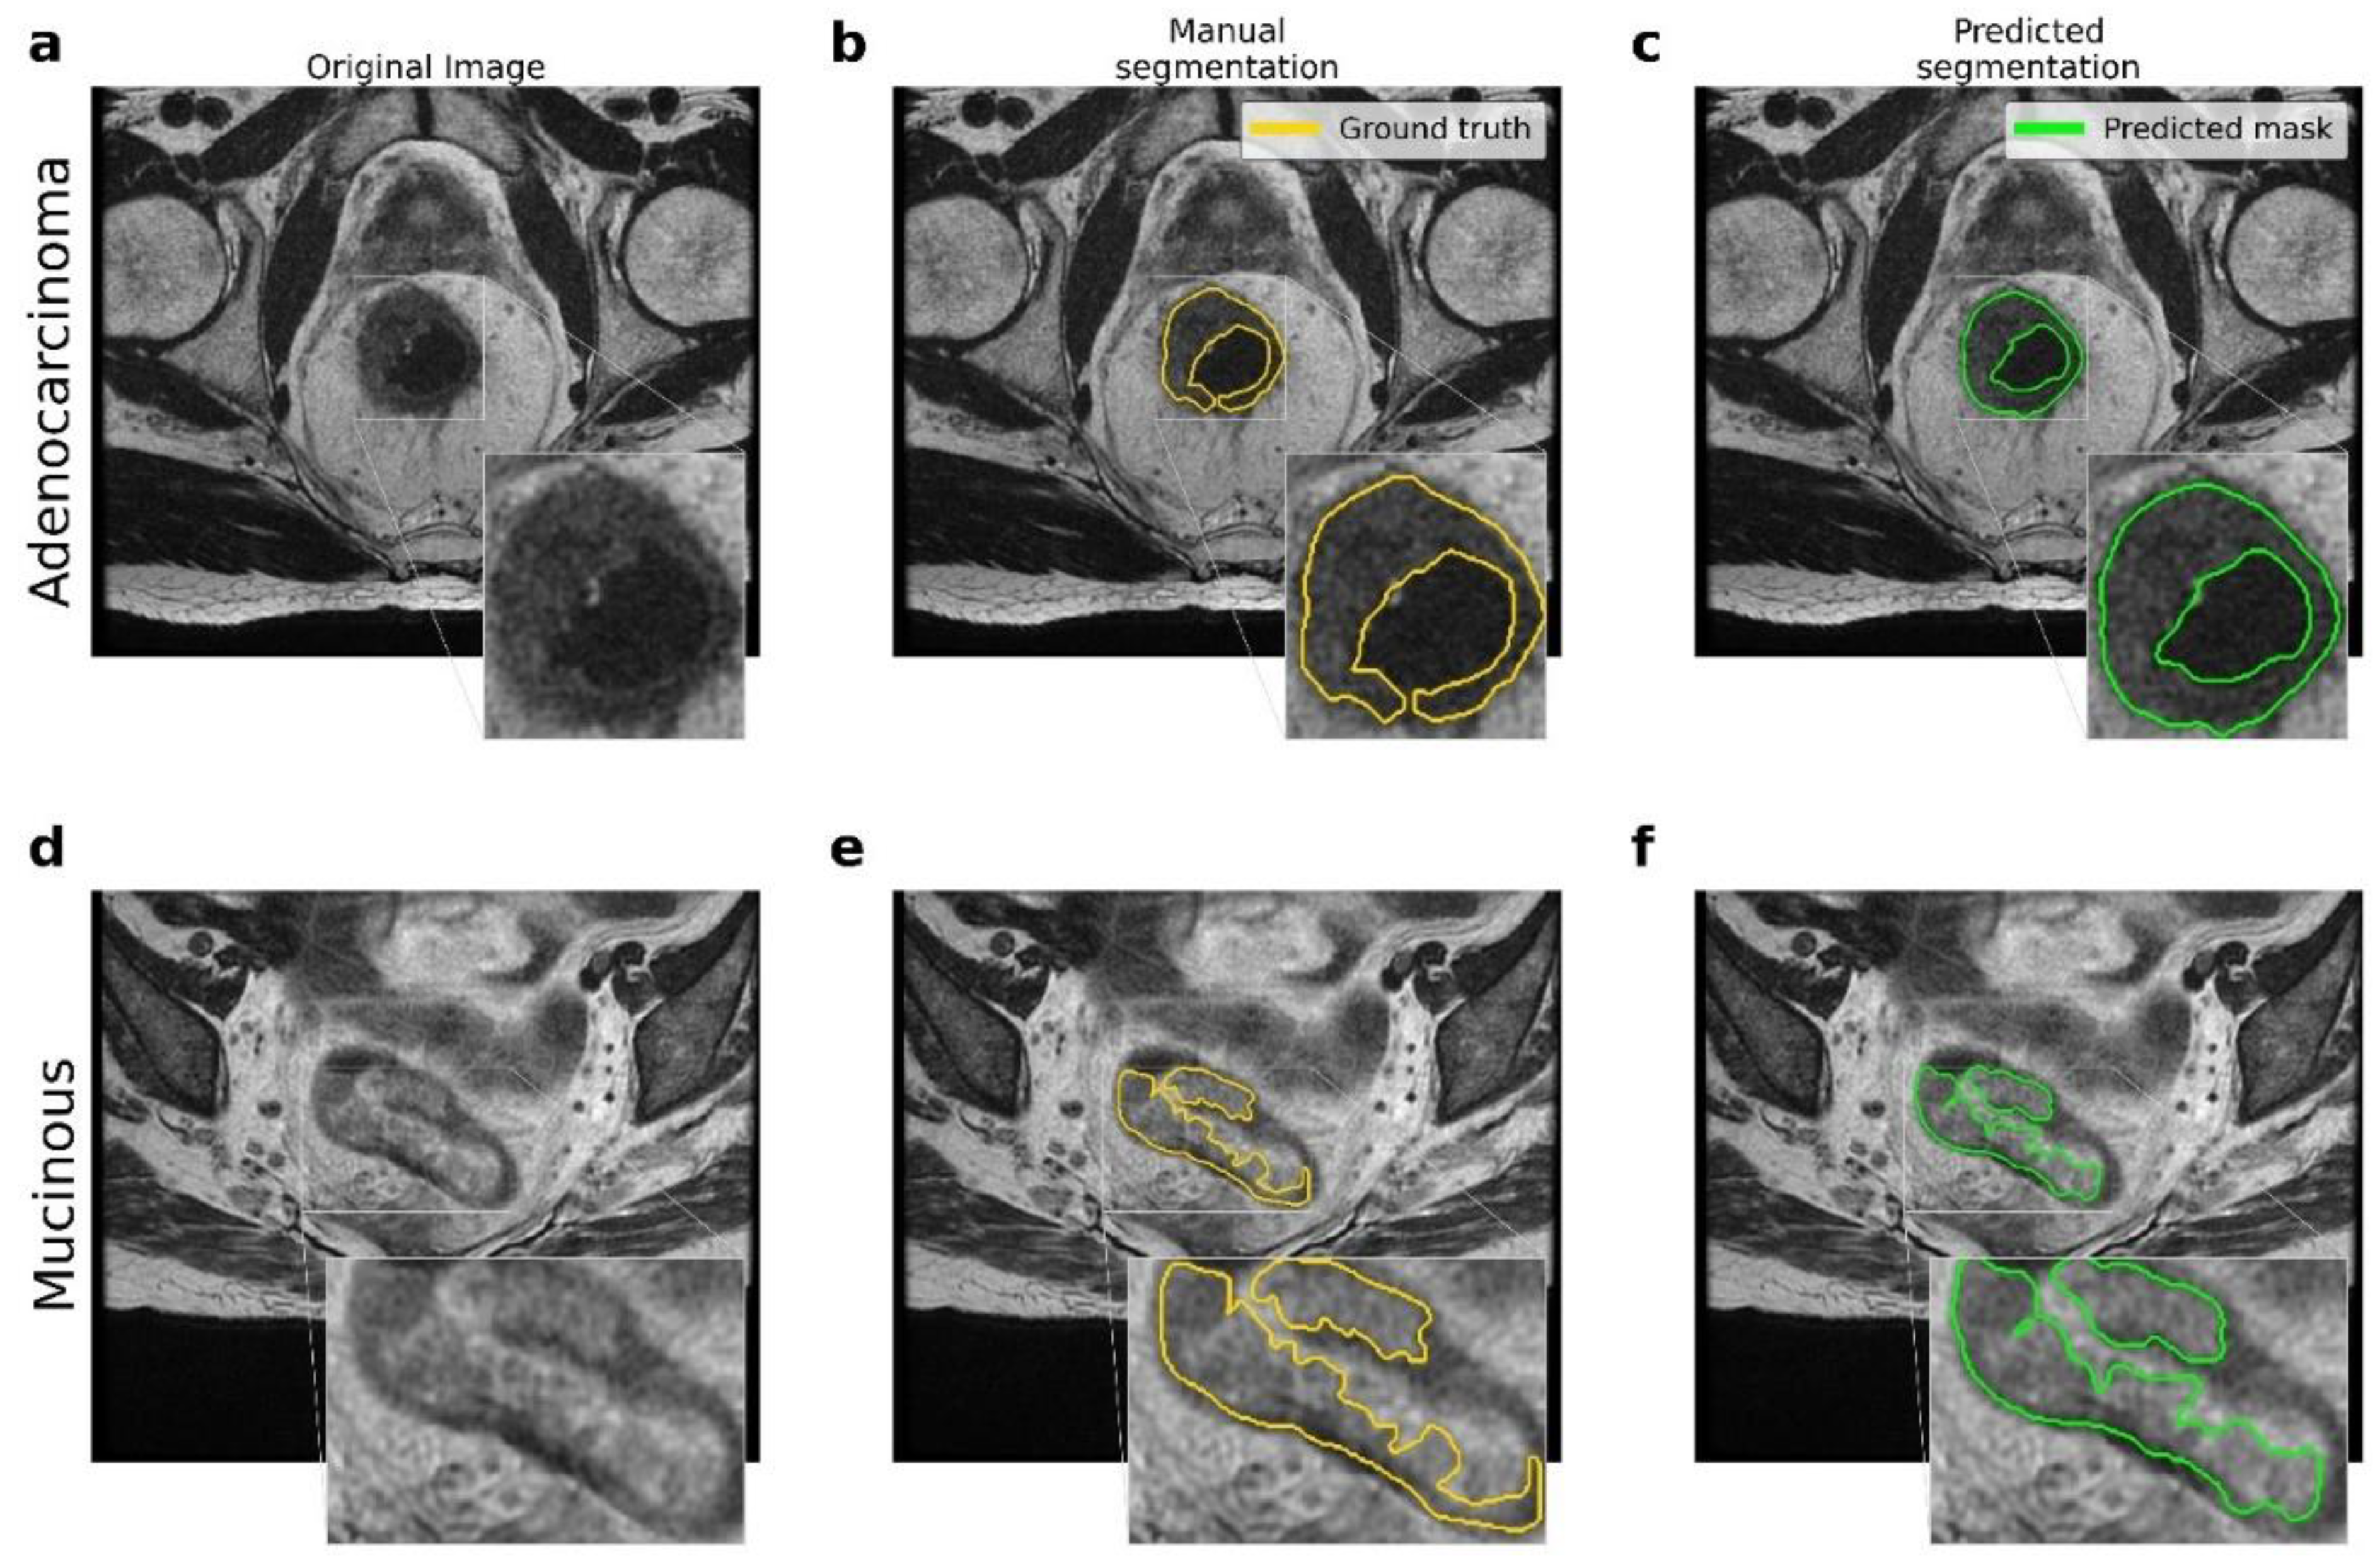

3.1. Rectal Segmentation